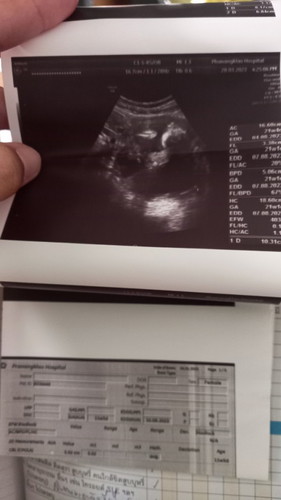

ตามนั้นเลยค่ะ ช่วยดูหน่อยค่ะ มองไม่ออกจริงๆ ลูกหมูมันอยู่ไหนนน

ดูไม่ออกว่าส่วนไหนค่ะ ขาวๆน่าจะกระดูกซักที่ค่ะ